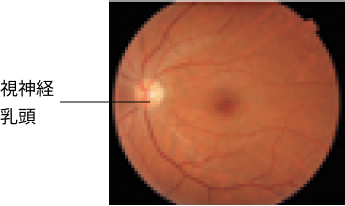

圧迫性視神経症を起こした甲状

腺眼症の眼底写真

視神経乳頭部に浮腫と出血がみ

られます。

Slentz DH, et al. JAMA Ophthalmol.

2021; 139(2): 244-247.